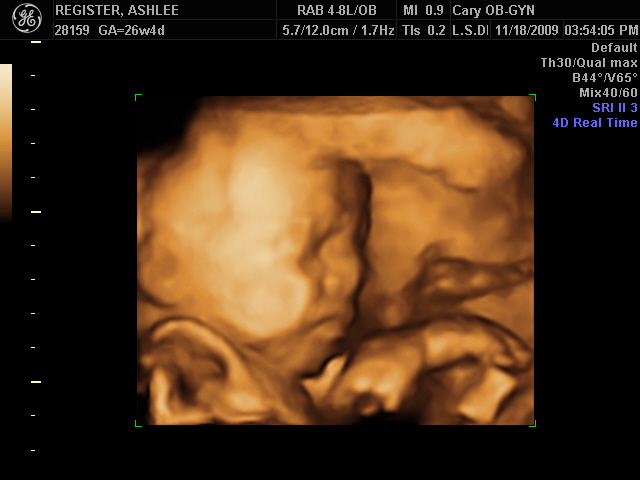

Today we went to the OB for our 26 week checkup. We had scheduled a 3D ultrasound session so that we could get a few pictures of our little girl & really get to see how she's doing in there! She has just started opening her eyelids in the past 2 weeks, & this picture catches her doing that! It's like she's saying "I see you looking at me!" The thing on the right side of her face is the umbilical cord.